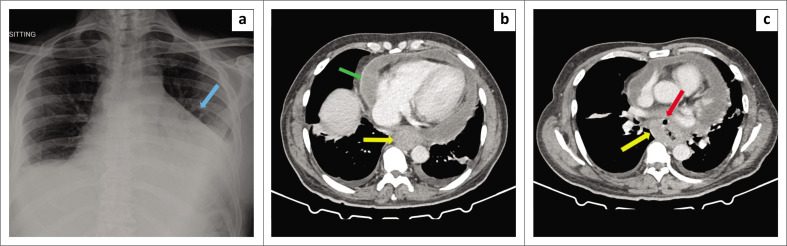

We describe the case of a middle-aged man and long-term smoker, presenting in cardiac tamponade with paroxysmal atrial flutter, with translocation of Candida glabrata into the pericardial space as a result of an erosive malignant oesophago-pericardial fistula.

Contribution: The isolation of Candida species from the pericardial space is a rare manifestation of invasive candida infection, carrying a high mortality rate, and requires interrogation for possible underlying immune aberrations or mechanical portals of entry.